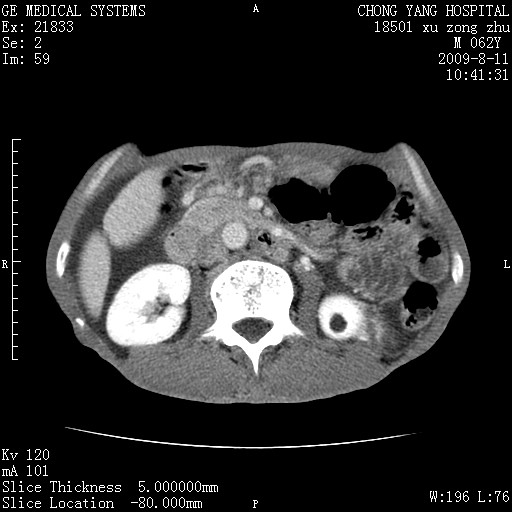

以下是引用杀毒软件在2009-8-11 16:35:00的发言:[br]肝内胆管扩张局限于左叶,胆管内有结石伴肝外胆管结石,胆管壁增厚呈弥漫性并发腹腔积液,胰腺边界模糊。[br][br]考虑---胆总管及肝内胆管结石继发胆管炎及胰腺炎,左肾下极囊肿,腹水。

以下是引用zjzjr在2009-8-11 17:35:00的发言:[br]肝内胆管扩张局限于左叶,胆管内有结石伴肝外胆管结石,胆管壁增厚呈弥漫性并发腹腔积液。[br][br]考虑---胆总管及肝内胆管结石继发胆管炎,左肾下极囊肿,腹水。